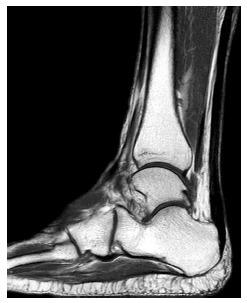

手术修复后跟腱的磁共振成像

MR Imaging of the Achilles Tendon after Surgical Repair.

Achilles tendon tear is common and increasingly frequent. Magnetic resonance imaging (MRI) is the modality of choice for radiological evaluation. It is accurate to assess the status and integrity of the tendon with well documented features. In this article, the MR findings of a normal Achilles tendon as well as common diseases like insertional and noninsertional tendinosis, chronic tendinosis with marked lengthening, tendon rupture are illustrated. After a torn Achilles tendon receives surgical repair, it undergoes different stages of healing process including inflammatory, reparative and remodeling phases. Acute scar tissue in the surgical bed may share similar MR features of tendon re-rupture especially in the early healing phase because both are T2W hyperintense. The size of the gap may even appear larger than expected on T2W images possibly due to tendon remodeling. Understanding of the healing process in post-operative period may prevent overestimation of tendon gap and misdiagnosis of re-tear. We describe the MR features of the post-operative changes with serial studies in different months after surgery. The MR findings with the highlights of the expected sequential changes in normal healing process are illustrated in different cases. A case with surgical repair on a partial tear of Achilles tendon is also included.

摘要

跟腱撕裂很常见且愈发频发。磁共振成像(MRI)是放射学评估的首选方式。它能够准确评估肌腱的状态和完整性,且具有充分记录的特征。在本文中,展示了正常跟腱的磁共振成像表现以及诸如附着点和非附着点肌腱病、伴有明显延长的慢性肌腱病、肌腱断裂等常见疾病的表现。跟腱撕裂接受手术修复后,会经历不同的愈合阶段,包括炎症期、修复期和重塑期。手术部位的急性瘢痕组织可能具有与肌腱再次断裂相似的磁共振成像特征,尤其是在愈合早期,因为二者在T2加权像上均呈高信号。在T2加权像上,间隙大小甚至可能看起来比预期更大,这可能是由于肌腱重塑所致。了解术后愈合过程可避免对肌腱间隙的高估以及对再次撕裂的误诊。我们通过对术后不同月份的系列研究来描述术后改变的磁共振成像特征。在不同病例中展示了磁共振成像表现以及正常愈合过程中预期的连续变化要点。还纳入了一例跟腱部分撕裂手术修复的病例。